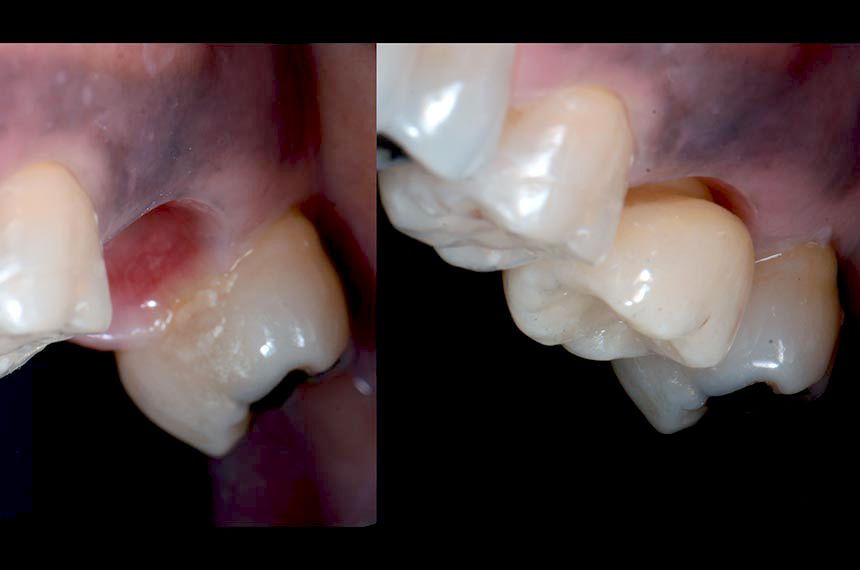

A major challenge encountered while undertaking immediate implantation in the molar area is the complexity of obtaining primary wound closure and coverage of the extraction site. Accordingly, this proposed protocol involves the chairside fabrication of a CADCAM abutment to seal the alveolar socket (SSA: Sealing Socket Abutment) immediately at the time of extraction-implantation (Finelle & al. 2016). Atraumatic flapless tooth extraction was performed by odontosection (Figs. 3,4) and separation of the supracrestal gingival fibers with periotomes. After extraction, the alveolar socket was liberally irrigated with sterile saline solution and cleaned with curettes to remove granulation tissue. A Straumann® Standard Plus Implant 4.8×12 WN was placed according to the instructions for use. The implant bed was prepared in the middle of the septum as virtually planned at the diagnostic stage (Fig. 5). The insertion torque was recorded during the placement and reached 30N/cm. Xenograft bone substitute (botiss cerabone®, granules 0.5-1mm, 1×0.5cc, Botiss) was packed to fill the alveolar socket surrounding the implant (Fig. 6). (Chu et al. 2012). To obtain closure of the socket at the time of extraction, an innovative protocol has been established to allow digital impression and immediate customized CADCAM abutment at the time of the surgery. A scan body (Cerec, Sirona) was connected to the platform of the implant to allow the intra-oral scanner (Omnicam, Sirona) to capture virtually the 3D position of the implant (Fig. 7). Immediately after acquisition, the SSA was designed on the prosthetic software (Fig. 8). The design process consists of: 1. Reproducing the outline of the previous freshly extracted molar in order to create a mechanical seal between the oral cavity and surgical site. The transmucosal portion is designed with a concave shape in order to accommodate for proper biological space (Finelle 2011, COIR). 2. Creating an ideal emergence profile to guide soft healing and positioning during the maturation process (Dual Zone concept Tarnow, Chu). The digital file was then exported to an in-office milling system (MCXL, Sirona) for fabrication of the SSA abutment (telio CAD 16, Ivoclar) in a chairside manner (Fig. 9). During the milling (15 minutes), sterile gauze was placed on the surgical site and post-operative recommendations were given to the patient. After milling, adhesive cement (Multilink abutment, Ivoclar) was used to assemble the SSA device onto the Variobase abutment for Cerec (Variobase C WN, Straumann) (Fig. 10). Finally, the SSA was inserted into the implant (with manual insertion torque) to support the surrounding soft tissues and provide a seal to the bone substitute material without the use of a biological membrane (Fig. 11)(Chu & al. 2012). Immediately after the surgery, post-operative periapical radiographs were taken to verify the proper position of the implant (Fig. 11). At the one week follow-up, the patient reported an uneventful post-operative recovery. The clinical examination at one week showed favorable soft tissue healing with minor inflammation (Fig. 12). After 12 weeks of osseointegration, soft tissue around the SSA abutment was healthy, and the buccal contour was maintained (Fig. 13). Removal of the abutment at the time of impression-taking showed a healthy and anatomical prosthetic emergence profile and a well-designed transmucosal portion (Fig. 14). A digital impression (Omnicam, Cerec, Sirona) using Scanbody for Cerec was taken for implant-supported restoration (Fig. 15). Finally, an implant screw-retained crown was designed (Fig. 16) on the Cerec Software (Cerec 4.4) and milled out of a monolithic lithium disilicate block (Emax CAD, Ivoclar) (Kapos & al. 2014). Before sintering, a blue CAD crown was tried in to validate the shape, contact point and occlusion (Figs. 16). The emergence of the implant screw axis allowed for a screw-retained prosthesis as originally planned (Fig. 17). The crown was stained and the occlusal grooves were readjusted to improve occlusal anatomy. The implant crown was bonded to a titanium base abutment adapted for the Cerec implant block (Variobase C, Straumann) with a resin cement (Multilink Hybrid Abutment, Ivoclar). At the time of final crown delivery (Fig. 18), we noticed the adequate emergence profile of the peri-implant soft tissues precisely fitting with the transmucosal anatomy of the ceramic crown. Final insertion torque (35N/cm) was applied, and the access hole was covered with restorative composite (Gænial A2, GC) (Fig. 19). A post-operative periapical radiograph was taken to verify the seating and marginal integrity after insertion (Fig. 19). While #27 was undergoing restoration, #36 and #37 were treated by surgical and restorative procedures, and two screw-retained single crowns were inserted (Fig. 20) in order to restore adequate prosthetic space (Fig. 21).

At the 6 month follow-up, the clinical situation was stable. No biological or technical complications were reported. Clinical assessment showed a stable soft tissue position and volume (buccal contour and papilla). This case report demonstrates the clinical benefits in terms of the surgical and prosthetic aspects of the molar treatment after extraction: 1. Surgically, the CADCAM device behaves as a mechanical barrier that ensures stabilization of the blood clot in a confined alveolar socket space favorable for the regeneration process. The SSA aims to “seal” the socket without the use of invasive techniques such as flaps, incisions and sutures. As there is no attempt at a primary closure procedure, the mucogingival junction is not displaced and the papilla architecture is maintained in its original anatomical position. Consequently, post-operative discomfort is expected to be very low. 2. From a prosthetic standpoint, the transmucosal portion of the SSA is shaped as described: a. Submergence profile (closer to the implant) with a narrow portion to accommodate for biological space and proper soft tissue healing (Finelle & al. 2015). B. Emergence profile (closer to the cervical margin) matching the anatomy of the previous existing natural crown (Chu & al. 2012).